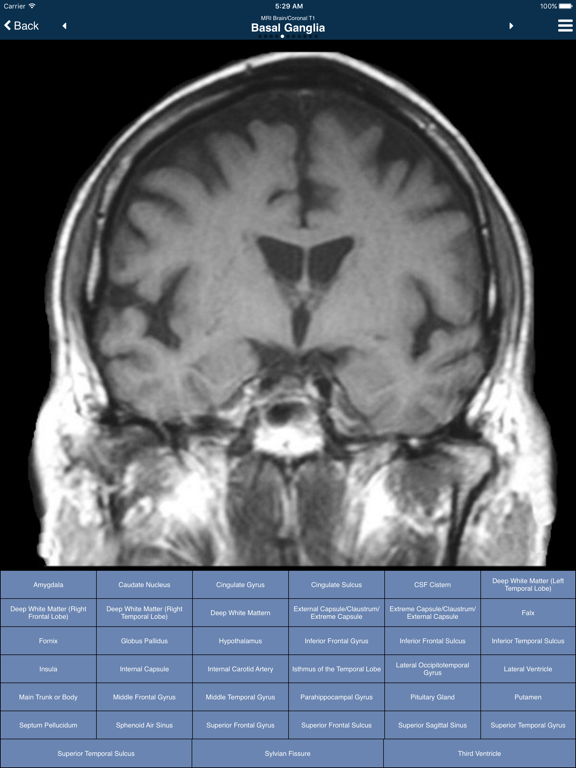

Note: This is the "lite" edition of the app, containing all of the Normal Imaging and a small number of Cases.

Welcome to Nina, the Neuroimaging In Neurology App! This app contains more than 600 images collected from normal individuals and patients with a variety of neurological and neurosurgical disorders. The goals of this app are threefold:

* to learn normal neuroanatomy from normal imaging;

* to recognize the imaging features of the most common and classic neurological disorders; and

* to learn some key clinical points about each disorder.

The app is divided into two main sections:

1) Normal Imaging

This section contains Magnetic Resonance Imaging (MRI) of the Brain, MRI of the Spine, Magnetic Resonance Angiography (MRA), Magnetic Resonance Venography (MRV), Computed Tomography (CT) of the Brain, and Conventional Angiography.

For most of the images, the native scan is shown without any labels. Buttons are shown labeled with anatomic areas of interest. Clicking on the button will cause the anatomy to be highlighted on the image. Also, clicking on the image itself will highlight the anatomy, display the name, and also light up the corresponding button. Users can quiz themselves by going through the names and the anatomy, in both directions.